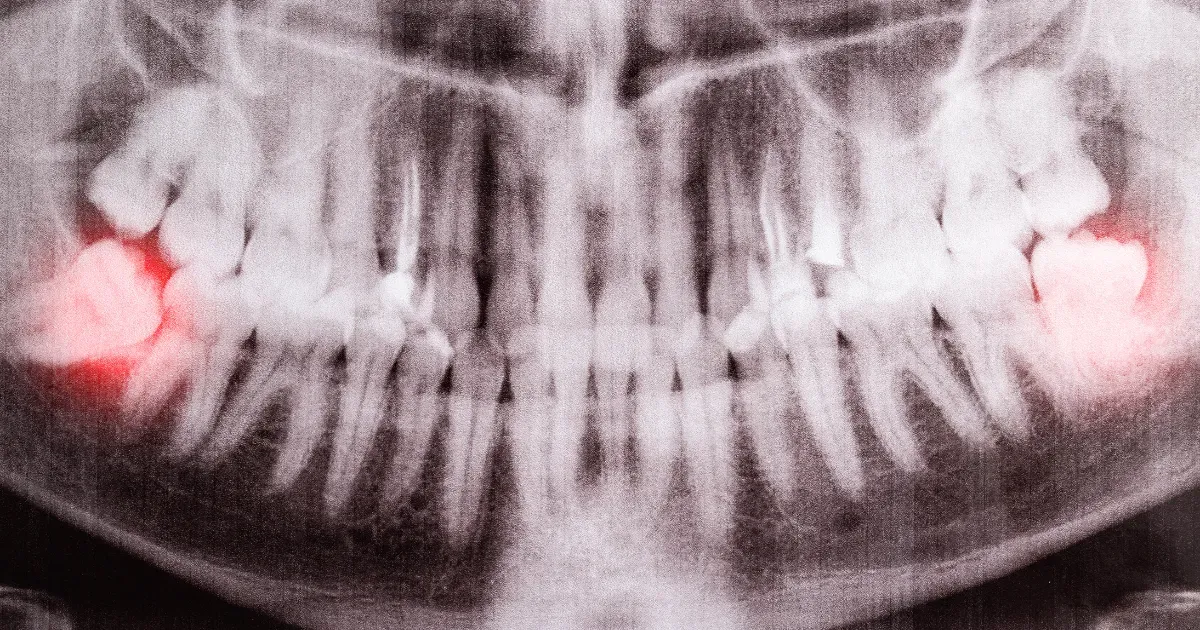

親知らずが埋まっているかどうかは、レントゲンやCTスキャンによって正確に確認できます。

歯の根っこの方向や、隣接する神経(下歯槽神経)や隣り合う歯との位置関係を把握するために、レントゲン撮影は非常に重要です。

レントゲン画像では、親知らずが完全に埋まっている場合でも、骨や歯の根の状態を確認できるため、抜歯の判断や治療計画の立案に役立ちます。

また、顎の骨の厚みや神経との距離も把握できるため、治療リスクを最小限に抑えるための情報を提供します。